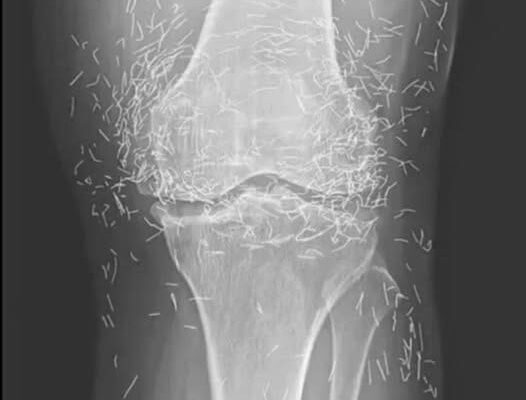

Years later, when doctors took X-rays to evaluate her knee condition, they weren’t prepared for what appeared on the images. Her knees were filled with dozens of bright, metallic flecks — tiny needles embedded deep within the joint area.

The findings were later documented in a case published by the New England Journal of Medicine.